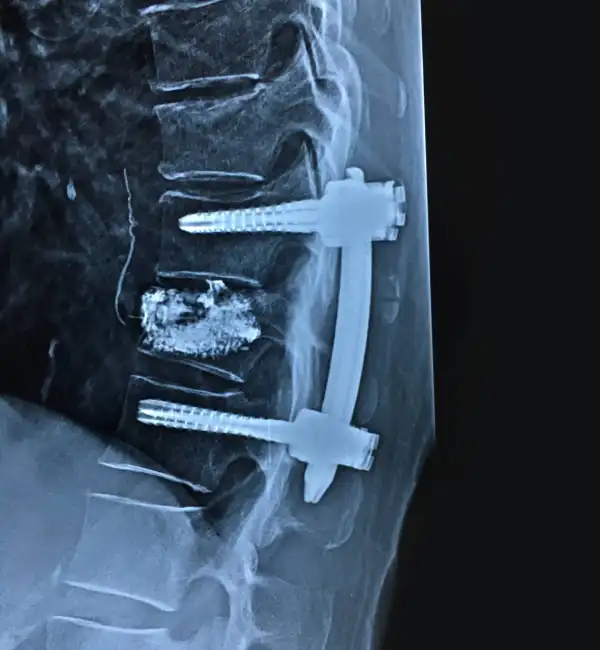

MIS Stabilization Vertebroplasty

Vertebroplasty With Instrumentation